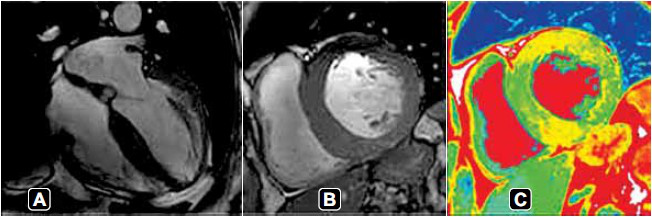

Paciente idoso, sexo masculino, 71 anos, portador de hipertensão arterial sistêmica e sem relato de outras comorbidades, com queixa de macroglossia, episódios de diarreia alternada com constipação, em uso de tipoia (tratamento conservador) após rotura espontânea do tendão do bíceps, procura o ambulatório com queixa de parestesia de membros inferiores.

Durante investigação etiológica, realizou uma ressonância cardíaca, apresentada a seguir.

A principal hipótese diagnóstica é: